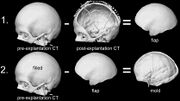

| 04:07, 8 April 2014 | Skull.jpg (file) | 66 KB | The doctor uses a CT scan of the patient’s skull before surgery (often taken upon onset of cranial trauma), then takes another after the flap of skull has been removed. Through digital subtraction of the two images, the flap’s shape can be determined, | |